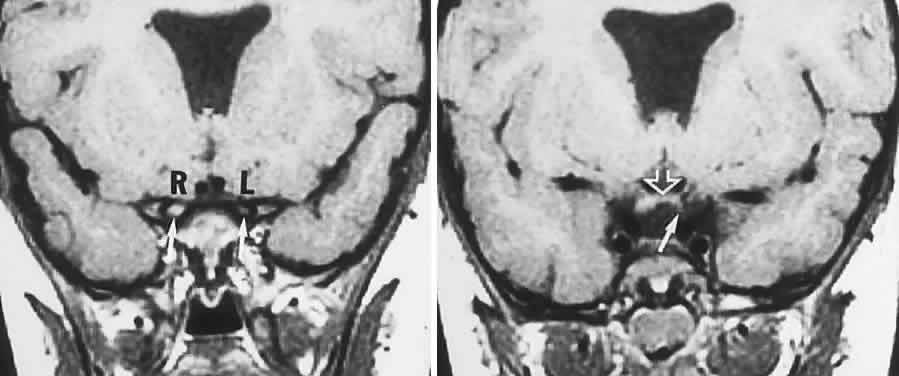

In contrast to transient symptoms and signs of retinal microembolic episodes, a condition of chronic ocular hypoxia (ocular ischemic syndrome) occurs less frequently, resulting from diffuse vascular occlusive disease of the aortic arch or common carotid artery. Acute or chronic occlusion with insufficient collateralization produces an ischemic pseudo-inflammatory uveitis, which variably includes an injected painful globe, corneal edema, aqueous flare and cells, a mid-dilated fixed pupil, rubeosis and iris atrophy, rapidly advancing cataract, either hypotony or elevated intraocular pressure (“neovascular glaucoma”), retinal microaneurysms and new vessel formation, posterior pole and mid-peripheral blot hemorrhages, macular edema, venous dilation and “sausaging,” cytoid infarcts (cotton-wool spots) of the nerve fiber layer, and arterial occlusions (Fig. 7; see Table 4). The hypoxemic fundus changes constitute a picture of venous stasis (low-pressure) retinopathy, perhaps the commonest ocular sign of chronic carotid obstruction.

Fig. 7. Ocular hypoxia with subacute carotid occlusion. The patient complained of a painful red eye. A. Anterior segment shows an irregular, fixed pupil and iris rubeosis (arrows). B. Fundus demonstrates combined retinochoroidal infarction with acute excavation of the optic disc. Arteriography revealed right internal carotid occlusion.